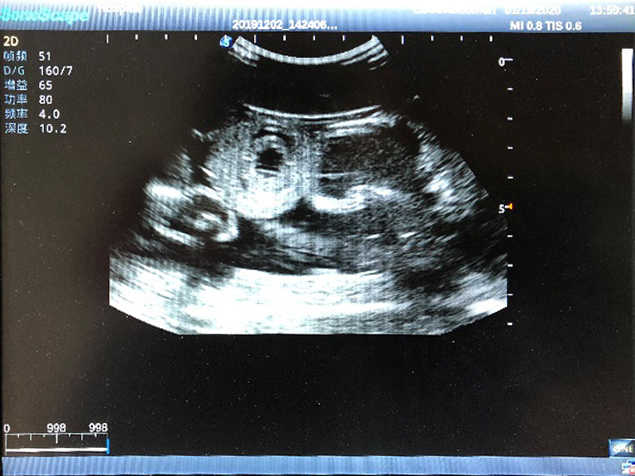

2)  High quality ultrasound image with clear structures like gallbladder, liver, intestines, arteries and veins etc.

5)  Normal & pathological ultrasound live and intestine models inside

6Durable for repeated use & easy replacement for consumable parts